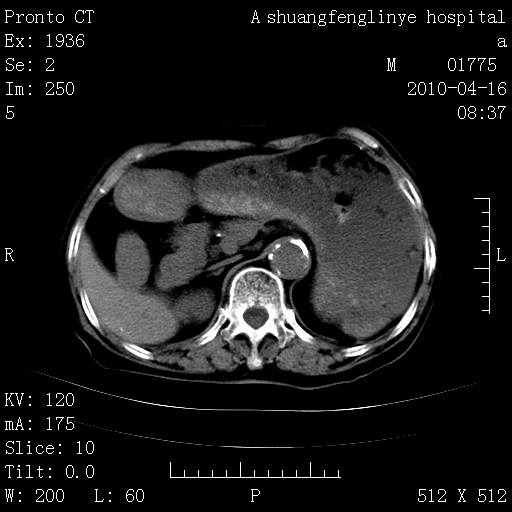

标题: CT25784:咳痰、请会诊!结核? [打印本页]

标题: CT25784:咳痰、请会诊!结核?

陈旧性结核,胃腔扩大,脾脏受压后移

慢支肺气肿,左上陈旧性结核,主动脉冠脉钙化

典型 夹层动脉瘤。 内膜瓣钙化移位

1)左肺上叶结核(纤维、增殖病灶)。2)冠状动脉及主动脉钙化。

1)左肺上叶结核(纤维、增殖病灶)。2)冠状动脉及主动脉钙化。肺动脉高压